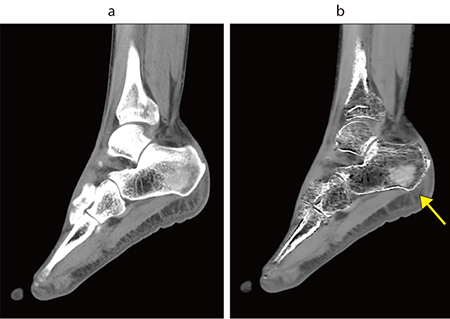

図1 踵骨 Dual Energy撮影

a:骨条件 b:VNCa

VNCa画像では骨折(↑)が確認できる。

Dual Energy撮影のVNCa画像で不顕性骨折を描出

同院では、整形外科領域の骨折、特にX線や単純CTでは判断が難しい不顕性骨折に対して、Dual Energy CT(DECT)を用いたVirtual Non Calcium(VNCa)画像での描出を行っている。同院では、増加する高齢者の骨折に対応するため、2024年に「高齢者骨折センター」を開設、手術からリハビリまで迅速かつ的確に診療を提供する体制を整えた。センター長を務める伊藤副院長はDECTについて、「X線や単純CTでは判断が難しい骨折でも、DECTのVNCa画像で明確に描出されるケースがあります。変性との違いを確認するためMRIは撮像しますが、CTでわかることで、より迅速な診断と治療方針の決定が可能です」と述べる。DECTは明らかな骨折を除いて骨折疑いの症例で撮影しており、椎体骨折や大腿骨近位部骨折、踵骨骨折、手根骨骨折などで有用だとのことだ。整形外科領域のDECTについては牧野医師も、「DECTで骨髄浮腫が明瞭に描出できるようになって、圧迫骨折や大腿骨頭の頸部骨折、緊急の腰椎ヘルニアなどの診断に有用です」と評価する。

DECT撮影は前機種の時から行っていたが酒井技師は、「Aquilion Serveでは、AiCE-iと非剛体位置合わせによって1回の撮影で診断が可能な画像を得ることができるようになり、安心して検査ができるようになりました」と述べる。また、酒井技師は、「VNCa画像は、救急の当直で整形外科の専門医以外が担当する場合に骨折がわかりやすく、入院などの的確な判断が可能です。休日や夜間は緊急でMRIを撮ることが難しいこともあり、CTで対応できるメリットは大きいですね」と述べる。DECTについては、今後、整形外科だけでなく口腔外科での骨折や出血の判定などにも展開していきたいと酒井技師は言う。